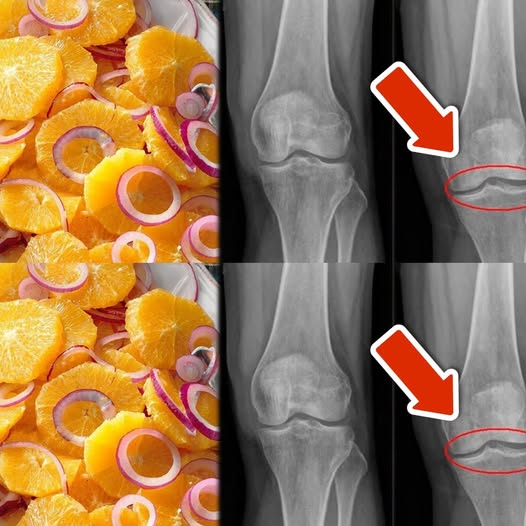

Zdrowe kolana, chrząstki i więzadła to podstawa codziennej mobilności i komfortu. Wiele osób szuka naturalnych sposobów na wzmocnienie stawów i redukcję bólu, a odpowiednia dieta może odegrać kluczową rolę w regeneracji tkanek. Ten prosty przepis na mieszankę pomarańczy i czerwonej cebuli to doskonały sposób na dostarczenie organizmowi składników odżywczych wspierających stawy. Zawarte w nim witaminy, minerały i antyoksydanty wspierają elastyczność i zdrowie więzadeł. Przekonaj się, jak łatwo możesz wprowadzić ten naturalny eliksir do swojej diety.